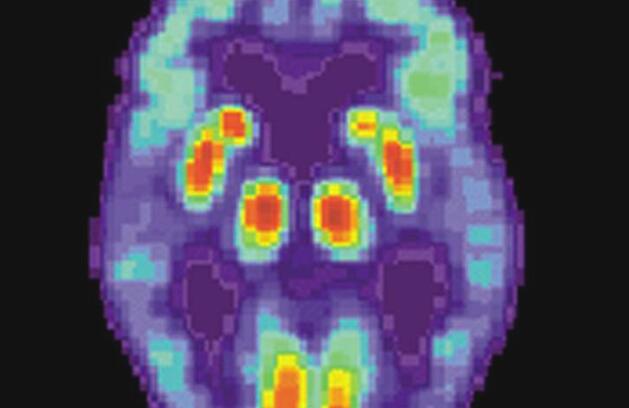

痴呆症最普遍的形式是阿尔茨海默氏病,导致神经细胞死亡和整个大脑的组织损失,从而导致记忆力下降,性格改变和日常活动中的问题。

需要严格调节蛋白质以使其正常运行。当这种质量控制过程失败时,蛋白质就会错误折叠,从而引发连锁反应,导致脑细胞死亡。错折叠的蛋白质会形成异常斑块,称为斑块,聚集在脑细胞之间,阻止它们正确发出信号。垂死的脑细胞还含有缠结,扭曲的蛋白质链,破坏了至关重要的细胞运输系统,这意味着营养物质和其他必需品不再能够通过细胞移动。